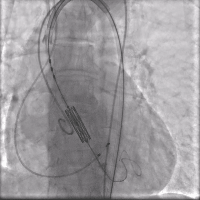

在快心室率起搏下平稳释放瓣膜,瓣膜释放过程稳定流程,瓣膜准确铆定于主动脉瓣环(视频3)。

术后造影(视频3)

停止起搏并撤回输送系统,撤出引导钢丝,关闭血管入路,术后造影及超声评价瓣膜功能良好,前向血流速度1m/s, 无明显瓣周漏(视频4)。